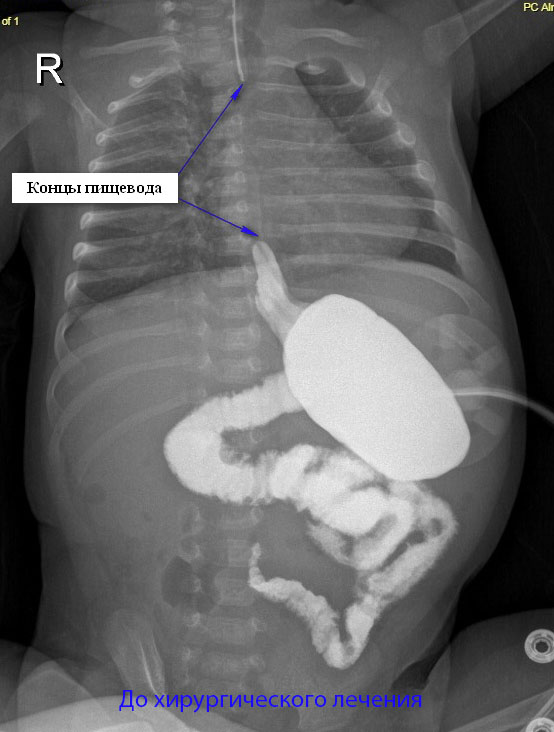

В Перинатальном центре Национального медицинского исследовательского центра имени В. А. Алмазова опытные врачи успешно помогают детям с различными патологиями, имея в распоряжении современное оборудование. Поэтому рожала петербурженка именно здесь. После родов врачи смогли провести обследование, которое показало, что у девочки очень редкая форма атрезии — бессвищевая (около 5 % от всех случаев атрезий). Атрезия пищевода — это тяжелый порок развития, при котором верхний и нижний сегменты пищевода разобщены и заканчиваются либо слепо, либо сообщаются с трахеей. При бессвищевой форме нижний сегмент пищевода очень маленький и ни к чему не прикреплен. По сути два конца пищевода не соединены между собой, а расстояние между ними порой настолько велико, что стянуть их невозможно. У данной пациентки — это расстояние составляло 5 грудных позвонков.

Не прибегать к использованию части кишки, а сохранить пищевод, соединив его концы, — очень сложно, а в некоторых ситуациях практически невозможно, поскольку расстояние между ними настолько большое, что пищевод при растягивании может порваться. Метод, позволяющий это сделать, появился относительно недавно с возникновением высоких технологий и эндоскопических видов вмешательств. Хирурги стали выполнять несколько малоинвазивных вмешательств, в ходе которых выделяют небольшие сегменты пищевода и сближают их между собой (насколько это возможно). Интервал между операциями составляет около недели. Через 6–7 дней наблюдается приживление этих сегментов, и их можно сблизить еще. После этого возможно уже соединить их между собой — создать анастомоз. У нашей маленькой пациентки удалось это сделать за два вмешательства.